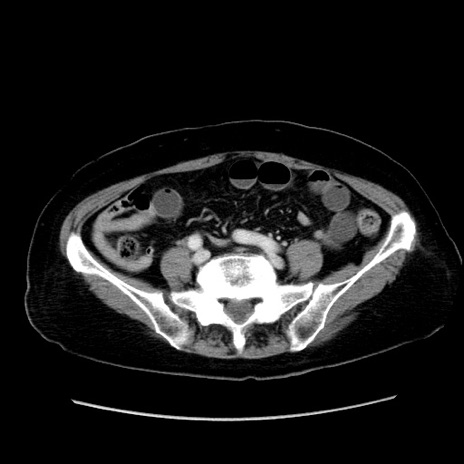

症例19(横断像)

【症例】80歳代女性

【主訴】下腹部痛

【現病歴】約8時間前より下腹部痛の出現あり、救急外来受診。

【既往歴】両側付属器切除

【身体所見】意識清明、下腹部正中に手術痕あり、その部位に一致して圧痛と反跳痛あり。腸蠕動音は亢進。

【データ】WBC 9300、CRP 0.15